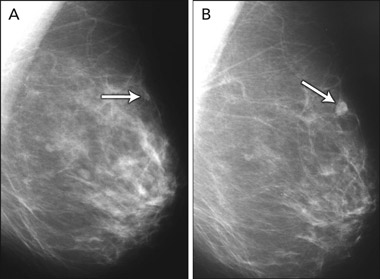

A meta-analysis of five studies of MRI as an adjunct to conventional imaging in high-risk women has provided convincing evidence that MRI detects additional cancers, with an incremental sensitivity of 58% (95% CI, 47%–70%) compared with mammography alone.15-20 Incremental sensitivity was lower when MRI was added to mammography combined with ultrasound examination (44%; 95% CI, 27%–61%) or to mammography combined with ultrasound plus clinical breast examination (range, 31%–33%).15 As summarised in Box 4, the addition of breast MRI led to the earlier detection of eight to 24 additional cancers per 1000 screens.15-20 Differences in MRI yield across studies reflected differences in comparator screening (mammography with or without ultrasound and clinical examination) and variations in disease prevalence. MRI provided the highest cancer yield when used in patients at highest risk.

The effect of detecting MRI-positive (mammogram-negative) cancers on breast cancer mortality, treatment morbidity or the incidence of interval cancers among high-risk (predominantly young) women has not yet been measured. Reductions in breast cancer mortality observed in trials of mammography screening among older, average-risk women have been attributed to the detection of breast cancer at an earlier stage, when the disease is more amenable to treatment. It is not yet clear whether earlier detection of cancers by MRI will bring the same benefits to high-risk women, who may represent a different prognostic group. Accuracy studies comparing tumour size and lymph-node spread between the extra cases detected by MRI and cases detected by conventional imaging alone have not provided consistent evidence that MRI produces a significant stage shift in the detection of breast cancer.15

4 Evidence on magnetic resonance imaging (MRI) as an adjunct to mammography (with or without ultrasonography) in screening young women at high risk of breast cancer